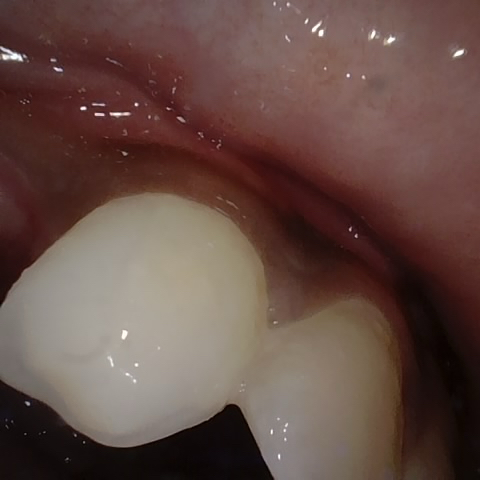

Annotated as "Good"